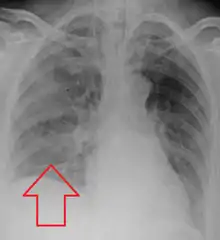

The location is often gravity dependent, and depends on the person's position. Generally, the right middle and lower lung lobes are the most common sites affected, due to the larger caliber and more vertical orientation of the right mainstem bronchus. People who aspirate while standing can have bilateral lower lung lobe infiltrates. The right upper lobe is a common area of consolidation, where liquids accumulate in a particular region of the lung, in alcoholics who aspirate in the supine position.[15]

Aspiration pneumonia is typically diagnosed by a combination of clinical circumstances (people with risk factors for aspiration) and radiologic findings (an infiltrate in the proper location).[1] A chest x-ray is typically performed in cases where any pneumonia is suspected, including aspiration pneumonia.[18] Findings on chest x-ray supportive of aspiration pneumonia include localized consolidation depending on the patient's position when the aspiration occurred.[18] For example, people that are supine when they aspirate often develop consolidation in the right lower lobe of the lung.[18] Sputum cultures are not used for diagnosing aspiration pneumonia because of the high risk of contamination.[19] Clinical symptoms may also increase suspicion of aspiration pneumonia, including new difficulty breathing and fever after an aspiration event.[6] Likewise, physical exam findings such as altered breath sounds heard in the affected lung fields may also be suggestive of aspiration pneumonia.[6] Some cases of aspiration pneumonia are caused by aspiration of food particles or other particulate substances like pill fragments; these can be diagnosed by pathologists on lung biopsy specimens.[20]